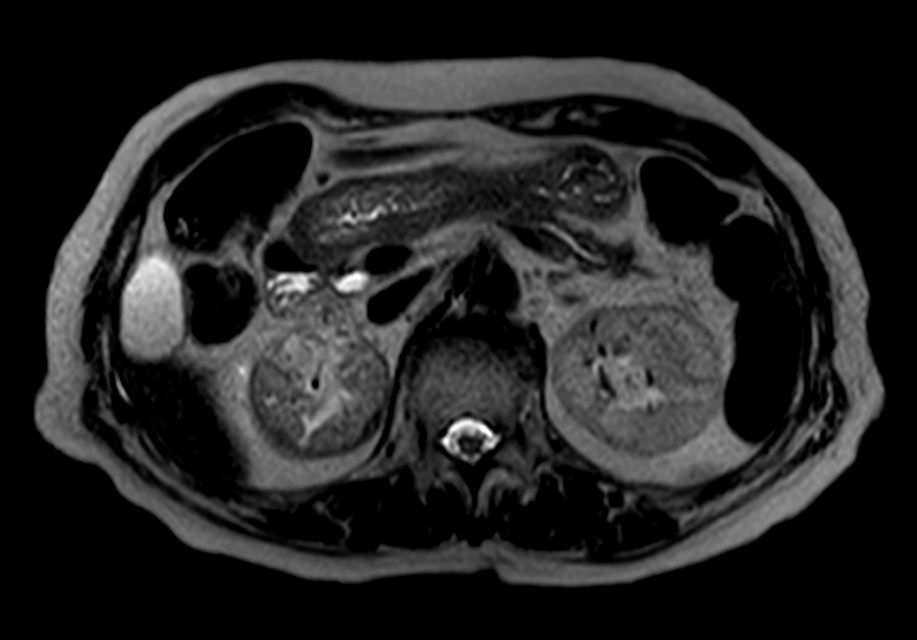

T2w SPIR MultiVane XD - Free Breathing

-